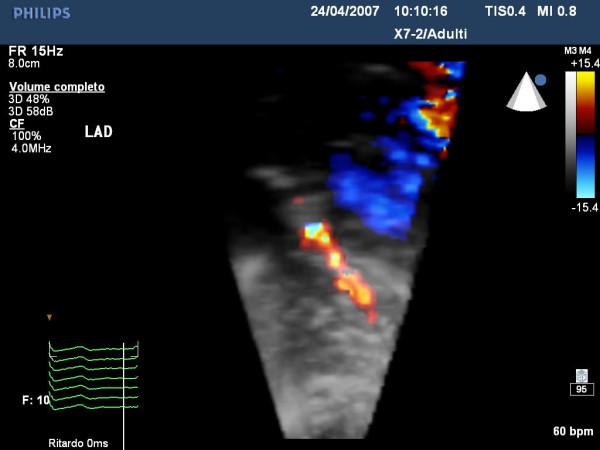

The aim of this paper is to highlight coronary investigation by transthoracic Doppler evaluation. This application has recently been introduced into clinical practice and has received enthusiastic feedback in terms of coronary flow reserve evaluation on left anterior coronary artery disease diagnosis. Such diagnosis represents the most important clinical application but has in itself some limitations regarding anatomical and technological knowledge. The purpose of this paper is to offer a didactic approach on how to investigate the different segments of left anterior and posterior descending coronary arteries by transthoracic ultrasound using different anatomical key structures as markers. We will conclude by underlining that, nowadays, innovative technology allows complete evaluation of both major coronary arteries in many patients in a resting condition as well as during pharmacology stress-tests, but we often do not know it.